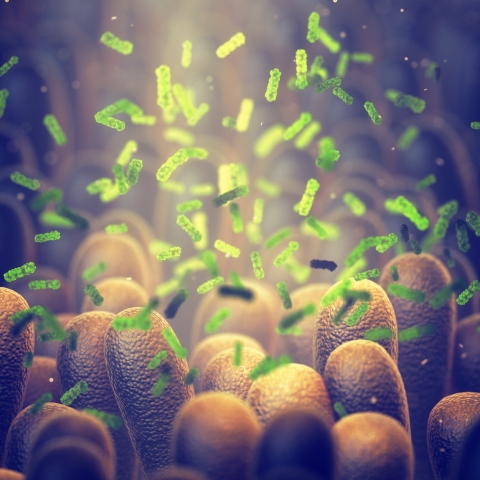

We're researching new ways to tackle the growing problem of antibiotic resistance to help prolong the lifespan and quality of life for people with chronic illnesses, and to more effectively treat millions of people around the world who have infectious diseases.

We're researching how microbes can cause infectious diseases and benefit human health, and tackling antibiotic resistance by identifying new molecules in pathogenic microbes.